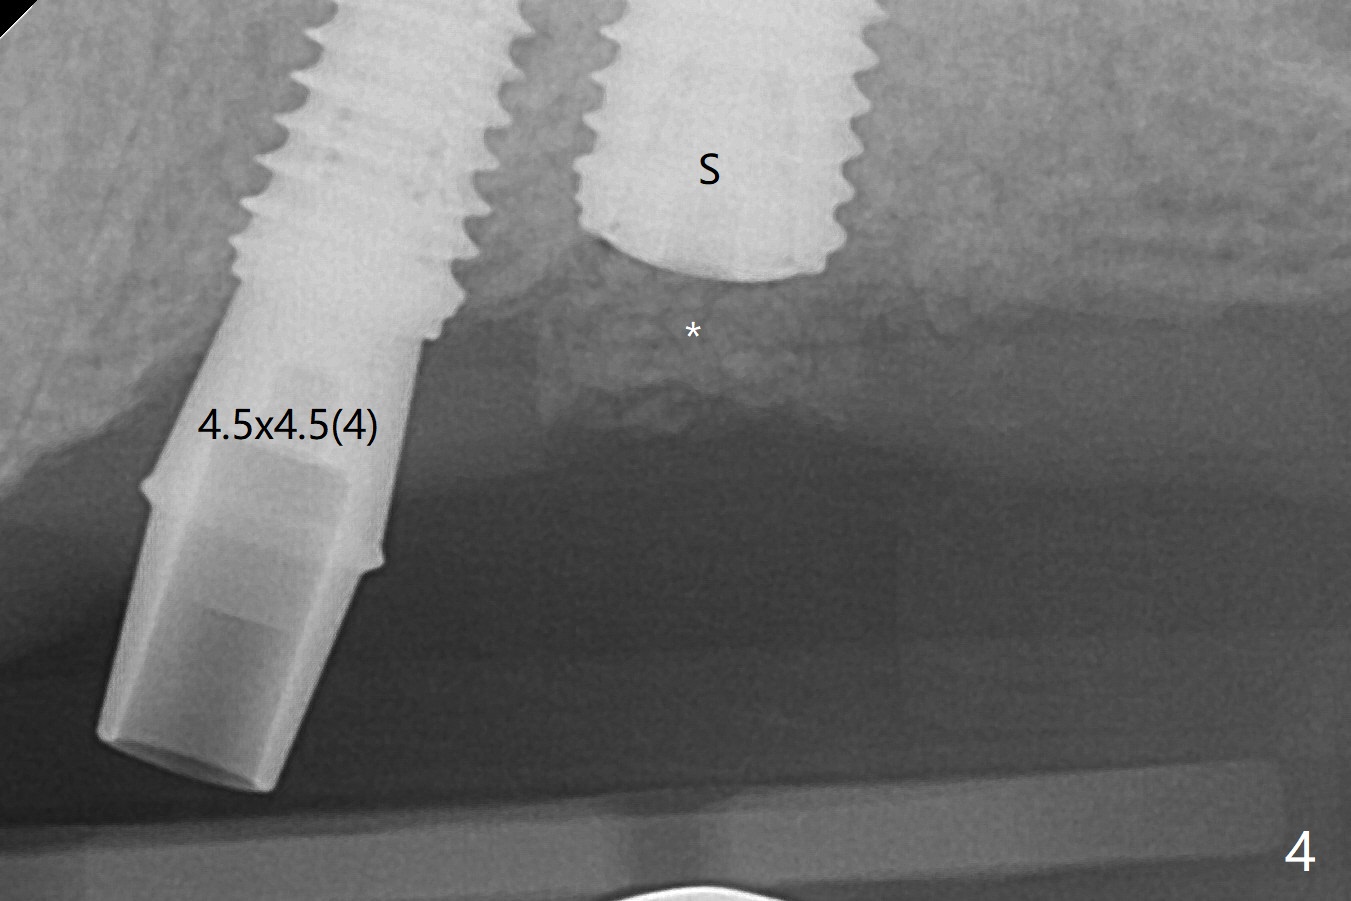

Three months post #14 implant removal and bone graft, the existing guide is reused, but no stop fixture mount cannot be inserted into #13 implant as an anchor. After 3.5x7.3 mm drill with 12 mm offset, the bottom of the osteotomy is not so hard; therefore sinus lift is conducted with allograft and 4x10 mm dummy implant (Fig.1). The lifted sinus floor is in fact not noted during the surgery (Fig.1 dashed red line). Sinus lift continues with bone graft and 4.5x10 mm (Fig.2); bone graft is squeezed out (*). The final implant (5x8.5 mm) is not seated until use of 4.5x7.3 and 4.0x10 mm drills (Fig.3). The implant is further placed free hand until subcrestal distal; since the torque is not high, a healing screw (S) is placed with packing allograft around the plateau of the implant (*). By placing a 4.5x4.5(4) mm cemented abutment at #13, a provisional is fabricated with extension to cover the bone graft at #14. When the provisional dislodges 1.5 months postop, #14 wound does not heal with the erythematous gingiva and exposed healing screw (Fig.5). Diabetes is not well controlled (HbA1c >6% (normal 4-5.6%)). Poor oral hygiene is another contributing factor in failure. After cleaning and torque 30 Ncm of the abutment at #13, impression is taken. In fact the tooth #12 has lost the palatal cusp (Fig.6 <); a crown will be fabricated at #12 when the implant at #14 osteointegrates. The implant at #14 is uncovered 5 months postop (Fig.7 (6.8x3 mm healing abutment)). The implants of #13 and 14 are close to each other, which is related to the slanted ridge at #13 (^). The osteotomy and the implant slide distal during placement (arrow). The implant in the slanted ridge should be intentionally placed mesial to compensate for the shifting. Or the ridge should be trimmed precisely; open surgery is necessary. A 5.2x5.5(4) mm cemented abutment is apparently completely seated with 35 Ncm torque 6 months postop (Fig.8). Although the distal plateau of the implant is exposed when the provisional is removed, post cementation bitewing shows equicrestal placement distal (Fig.9).